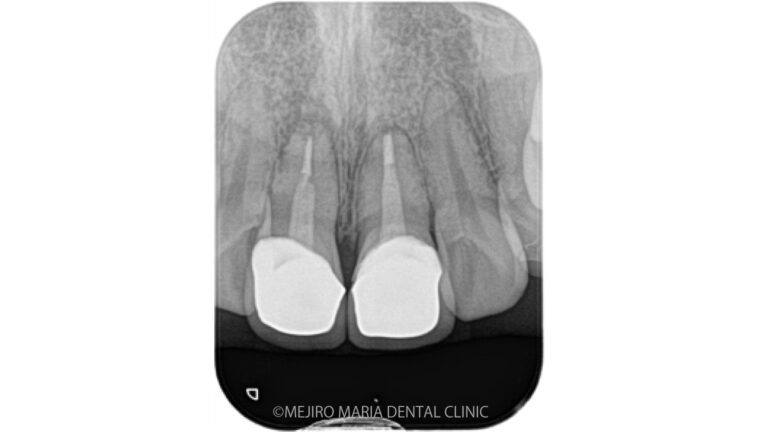

• メイン画像|【症例】セラミック治療後に発症した根尖性歯周炎に対する歯根端切除術|目白マリア歯科

【症例】セラミック治療後に発症した根尖性歯周炎に対する歯根端切除術